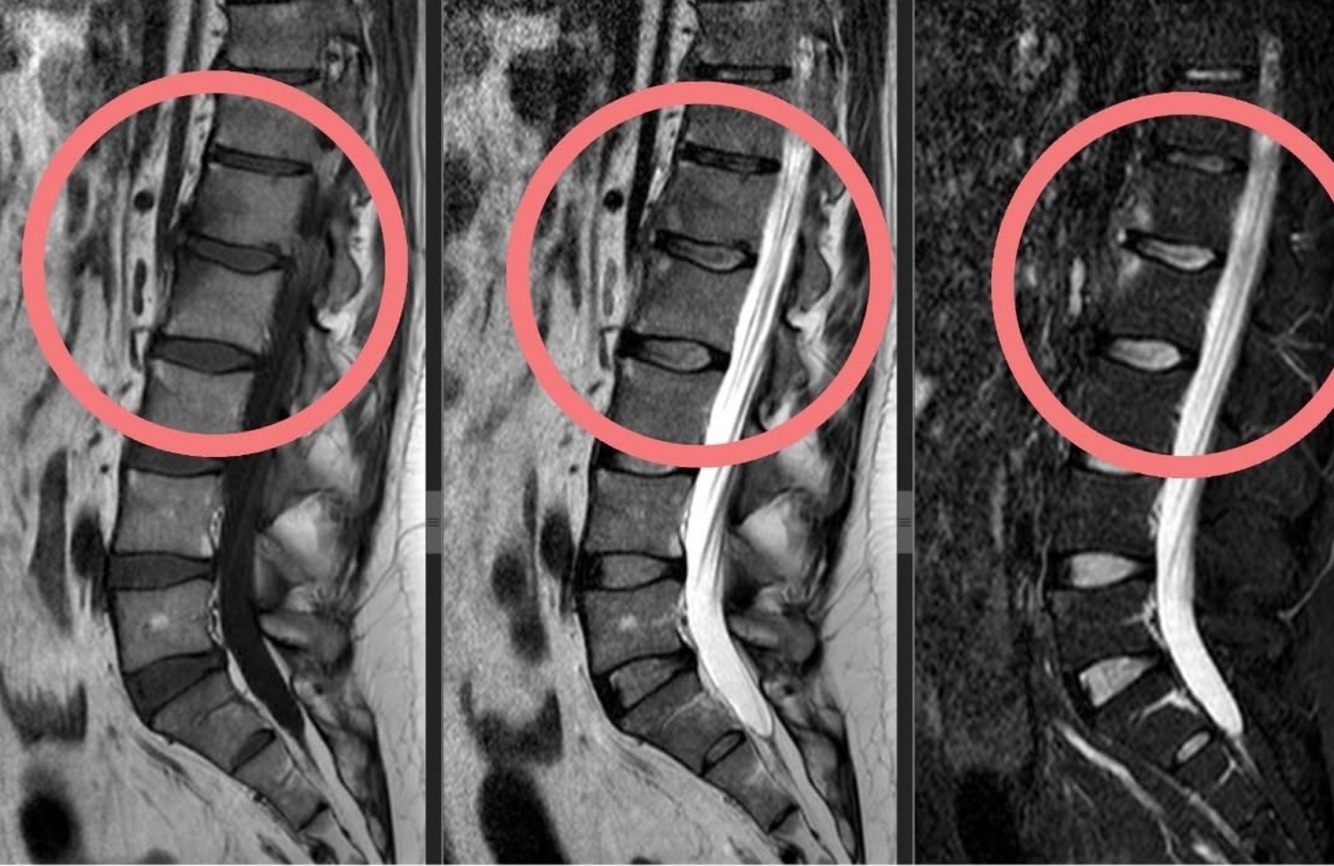

Qual a doença mais sugestiva da vértebra plana?

Histiocitose

Quais são os diagnóstico diferencias além da histiocitose para

Vértebra plana?

H- Histiocitose

E - Ewig (sarcoma)

I - Infecção

G - Gigante (TCG)

H - Hematológico

T - Tuberculose

O - Osteosegenese imperfeita

F- Fratura

H- Hemangioma

O - Osteoblastoma

M - Metástase

O - osteomilite crônica